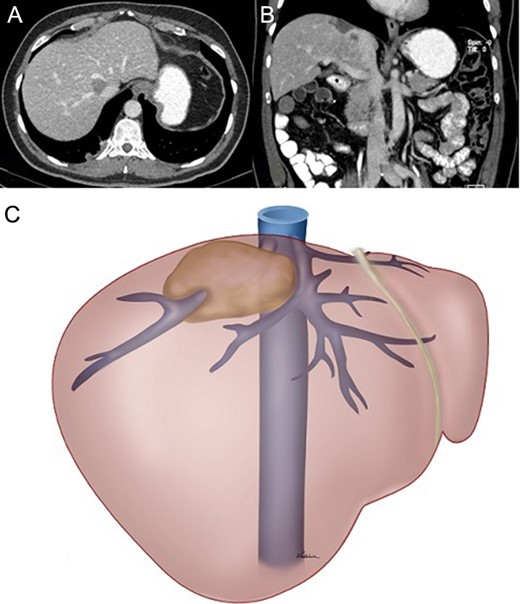

The parenchyma was transected using bipolar forceps under intermittent Pringle manoeuvre [7]. Transection started at the middle hepatic vein until it was released from the tumour, and proceeded posteriorly to release the tumour from the IVC. Right hepatic vein was cut close to the IVC and the IVC was sutured. The remaining parenchyma was transected and the right hepatic vein was skeletonized for a length of 1 cm to allow graft placement (Fig. 2). Subsequently, the open end of the graft was anastomosed in a standard manner to the IVC (Fig. 3).

(A) Right hepatic vein sutured close to the IVC. (B) Middle hepatic vein freed from the tumour. (C) Right hepatic vein within the transected area skeletonized for 1 cm. (D) Retrohepatic IVC, area to be anastomosed to one end of the graft. (E) Segment 8 with the tumour.